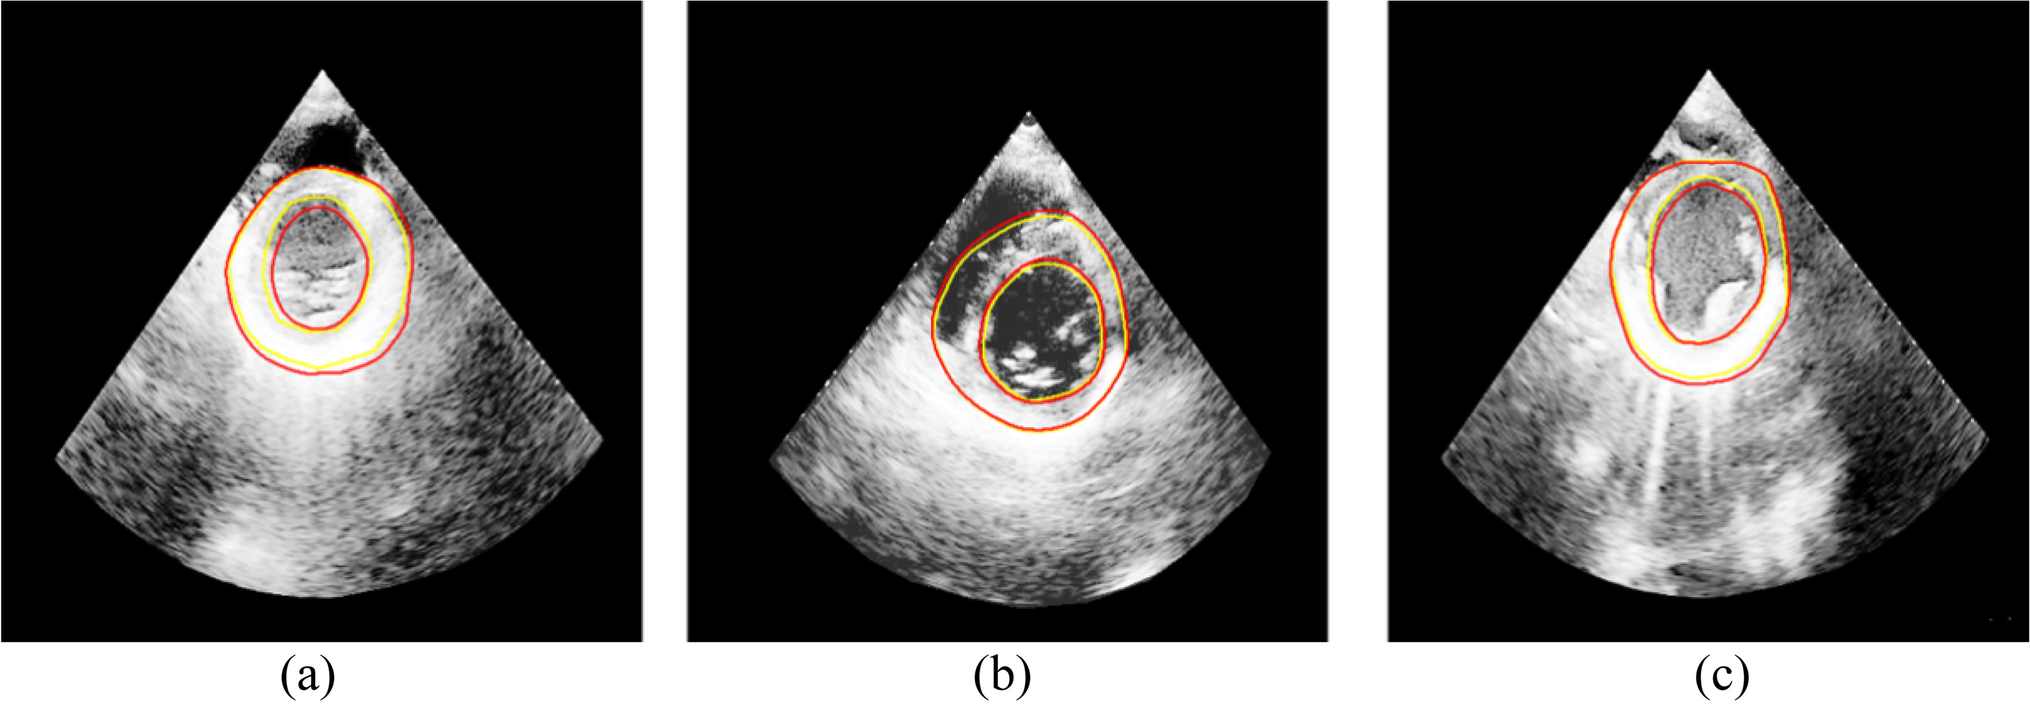

Since the ultrasound images suffer from low contrast and poor imaging quality, we performed image preprocessing, including mask operation and gray level equalization. We compare our method with other segmentation methods( U-net [18], R2U-net [33], Att U-net [34] and U-net +  + [21]). The above networks are reproduced by their original papers. The segmentation accuracy is shown in Table 2. The DSC of our method is 91.90%. Figure 5 shows the transverse plane segmentation results of echocardiography.

Fig. 5

The segmentation result, where the golden contours represent the real annotation result, and the red contours are the segmented image

We used the three types of medical images to verify the performance of the segmentation algorithm based on our method. The steps are as follows: First, we preprocessed the training image, including uniform image size and grayscale normalization. Second, we used the statistic shape model and 3D thin plate spline to achieve the purpose of data augmentation. Third, we constructed the medical transformer network structure to segment three types of medical images. The test results show that the segmentation algorithm proposed in this paper achieved a DSC of 89.97%, 91.90%, and 94.25% on the prostate MR images, heart US images and tongue color images, respectively.